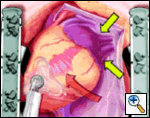

The pericardial sutures are withdrawn and the right hemisternum elevated by placing a folded towel under the lower right side of the sternal retractor, and an apical suction device (Urchin or Starfish [shown at left] Medtronic) attached to the cardiac apex. The heart is gently positioned similar to a ramus or high marginal coronary artery exposure. The left atrial appendage (LAA), and left sided pulmonary system should be in relatively clear view (LPA, LSPV, and LIPV).

An Ethicon 4.8 mm (Green load) NO KNIFE (NK) endo-GIA stapler is used to remove the LAA, passing the stapler from caduad to cephalad. Ensure hemostasis, though sutures are usually not needed. Total operative time is generally less than 15 minutes. OPCAB is then carried out in the usual fashion.